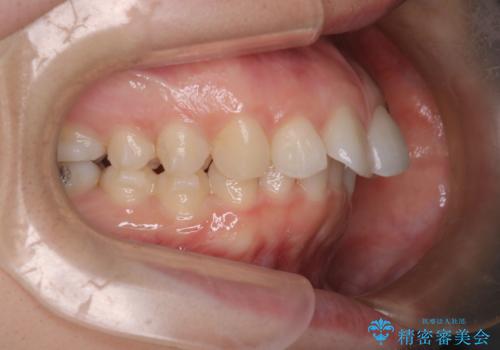

【インビザライン】前歯を引っ込めたい

- 前歯が出ていることを主訴に来院された患者様です。

抜歯を希望されなかっため、臼歯部の遠心移動やIPRを行い配列を行っています。

抜歯をしていない矯正となるため、口元に大きな変化は認められません。